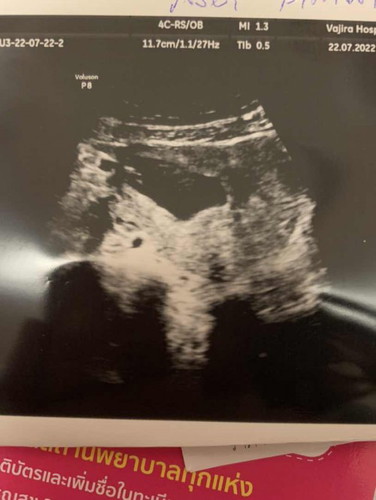

ช็อคมากท้องลม12week

อัลตร้าซาวน์ครั้งแรกค่ะ..ไม่เจอเด็กเจอแต่ถุงหมอบอกท้องลมค่ะ ทำใจไม่ได้ ช็อคมาก😢😢หมอนัดอีกที5สิงหาติดตามอาการ ถ้าเลือดยังไม่ออกหมอจะดูดถุงค่ะ

ชาวก็รุ้ค่ะ ถ้าท้องลมเด็กจะไม่มีตัวอ่อน ไม่มีเสียงหัวใจ 8-9วีค เด็กควรมีตัวอ่อนแล้ว